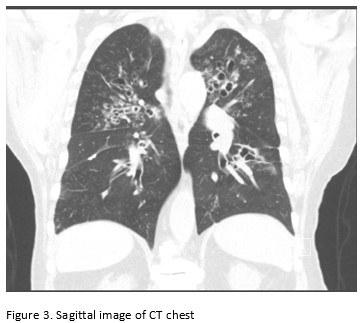

A 65-year-old male with poor healthcare follow-up presents to the pulmonary clinic with “years of breathing problems”. He reports shortness of breath and cough productive of grayish-brown sputum. He denies fevers, chills, weight loss, hemoptysis and night sweats. He denies recent travel history. His physical exam is significant for scattered wheezes bilaterally. Labs are significant for peripheral eosinophilia of cells/microL (21.7% eosinophils) and elevated total Ig E level of 2385 IU/ml. Representative images of his CT chest are shown below.

Images